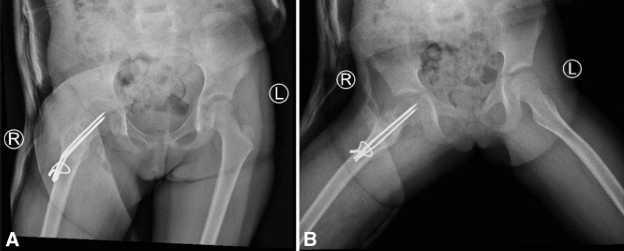

随访观察:随访期间发现,因患儿生长发育导致克氏针逐渐向股骨颈远端移位,使愈合周期延长——这恰是选用光滑克氏针而非螺钉的优势所在。图6展示了术后1年的影像资料。术后两年半,骨愈合完全,患者返院取出内固定物(图7)。内固定去除后1年随访显示(图8),股骨颈重塑至正常颈干角,末次随访时患者关节无僵硬、活动度无受限、无疼痛及跛行。